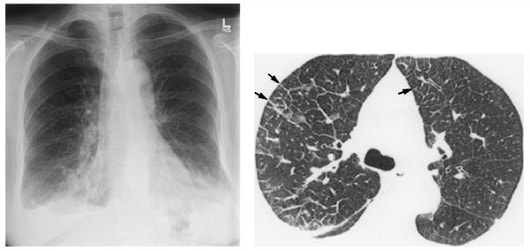

関節痛、筋肉痛、脱力の頻度は高く、受診のきっかけになります。障害されやすい臓器は、皮膚(紫斑と皮下結節が多い)、中枢神経、心臓(心筋梗塞、心筋障害による心不全)、心外膜、肺、胸膜、消化管(潰瘍や穿孔)などです。

一般的にステロイド薬治療によく反応します。プレドニンは、皮膚症状よりは重症のぜんそくや肺浸潤のほうに量を多く使い、中枢神経・消化器・心病変ではさらに多くなります。反応が悪い場合は少ないのですが、プレドニンを増量するか、ステロイドパルス療法、免疫抑制薬(エンドキサンなど)の内服などを加えます。抗凝固薬、抗血小板療法、血管拡張薬、血栄交換を併用することもあります。